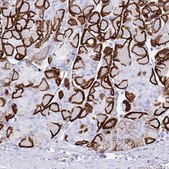

Application

The Human Protein Atlas project can be subdivided into three efforts: Human Tissue Atlas, Cancer Atlas, and Human Cell Atlas. The antibodies that have been generated in support of the Tissue and Cancer Atlas projects have been tested by immunohistochemistry against hundreds of normal and disease tissues and through the recent efforts of the Human Cell Atlas project, many have been characterized by immunofluorescence to map the human proteome not only at the tissue level but now at the subcellular level. These images and the collection of this vast data set can be viewed on the Human Protein Atlas (HPA) site by clicking on the Image Gallery link. We also provide Prestige Antibodies® protocols and other useful information.

- IHC tissue array of 44 normal human tissues and 20 of the most common cancer type tissues.